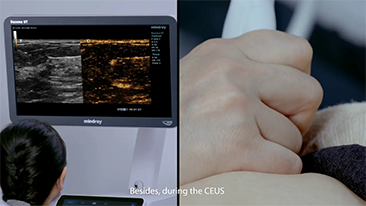

Jak wyra?nie mo?na zobaczy? w?trob??

W przypadku ogniskowych zmian w w?trobie, takich jak naczyniaki czy nowotw├│r w?troby, obrazowanie USG z kontrastem odgrywa wa?n? rol?. Technologia obrazowania USG z kontrastem UWN+ mo?e pom├│c uzyska? lepsz? penetracj?, lepsz? jako?? obrazu z ni?szym indeksem mechanicznym MI oraz d?u?szy obserwowany czas perfuzji.